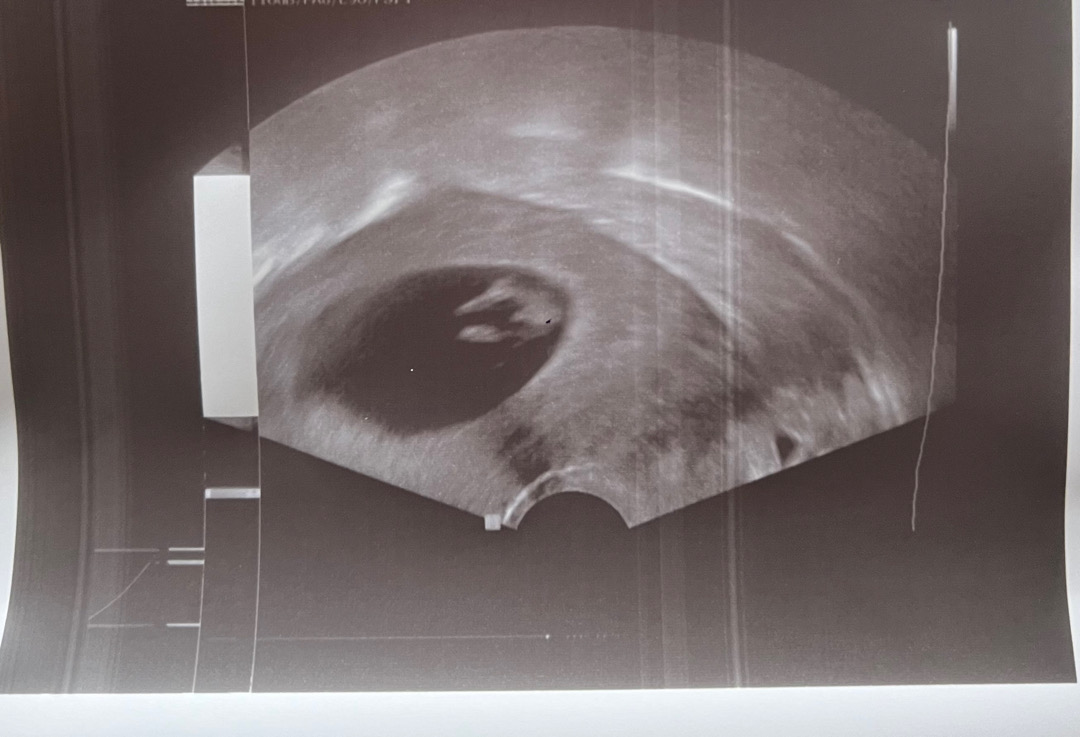

이 시기에 보이는 저것은 보통 탯줄이라고합니다 ㅎㅎ

오늘 초음파 찍었는데 다리사이에 ㅋㅋ

해외인데 의사선생님께서 보시더니 작은 페니스가 보이는 것 같다며 사진을 저렇게 찍어주셨어요 ㅋㅋㅋㅋㅋㅋㅋ 아직 10-11주차라 나중에 알게 되겠거니 했다가 갑자기 오늘 높은 확률로 아들일 수도 있다는 걸 알게 됐네요 ㅋㅋㅋㅋ 너무 신기해요

앜ㅋㅋ아 꼬리만 생각했는데 탯줄일수도있군요! 알려주셔서 감사해요 ☺️

지금은 딸이든 아들이든 생식기가 다 튀어나와있어용 ㅋㅋㅋ의사쌤이 너무 빨리 기대하게 말씀하셨네요

저두 10주3일에 성별 여쮸ㅓ봤는데 아직은 생식기가 다 튀어나와있을때라 모르신다했어요 ㅎㅎ

딸이나 아들이나 지금은 다 튀어나와있어요